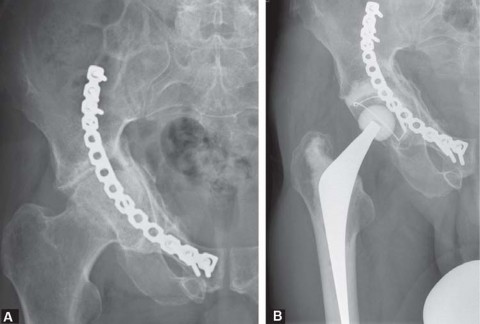

Introduction Total hip replacement is an important option in the management of sequelae following fractures o…